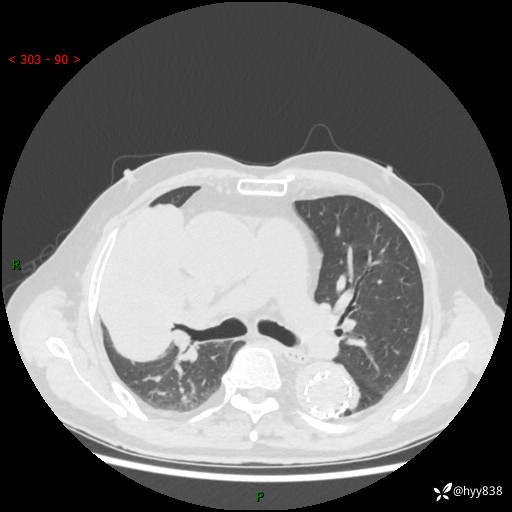

辅助检查:CT

胸部CT平扫